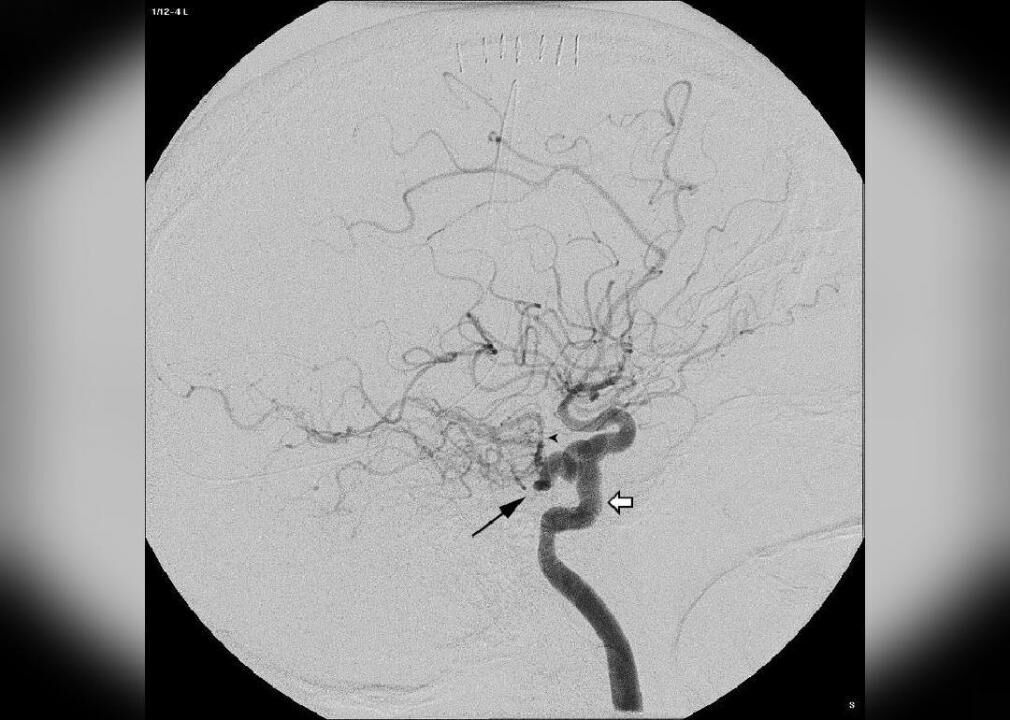

1933: Angiogram, barking mad

Norman Dott of Edinburgh, Scotland, produced the first angiogram in 1933, demonstrating a cerebral aneurysm. Author Raymond T. Pierrehumbert referred to the as ‘barking mad’ in 1933.